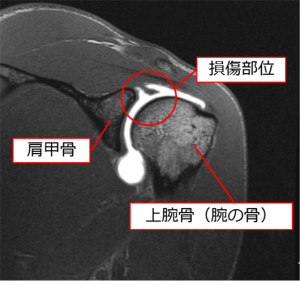

これは肩甲骨と上腕骨(腕の骨)が接している部分の図です。

何らかの原因で損傷を受けた部分を縫い合わせて修復します。